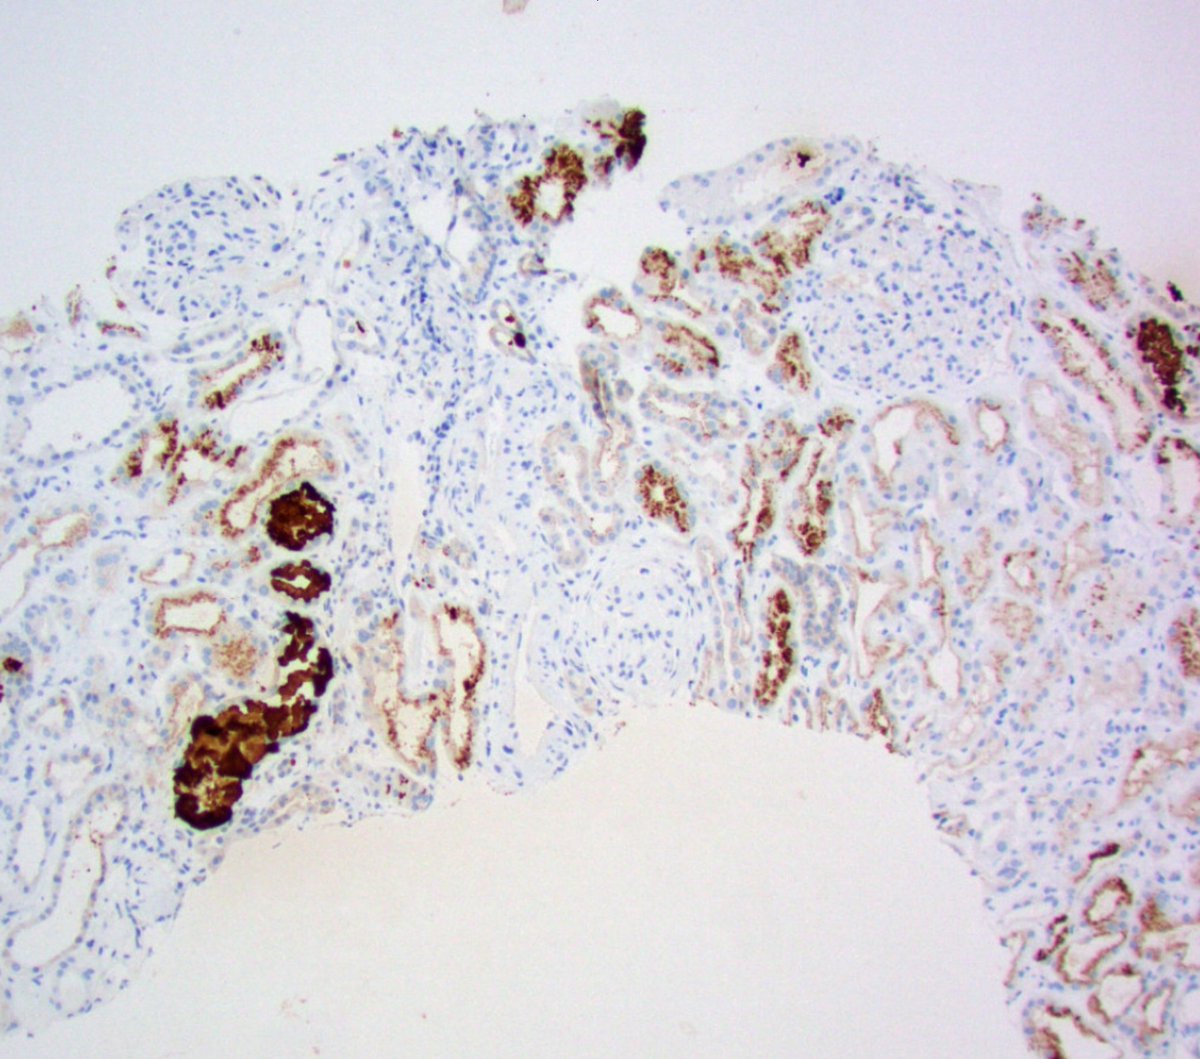

Teenager with nephrotic syndrome. Biopsy revealed unusual case of membranous nephropathy in a peds patient. PLA2R positive (IHC). PLA2R most common antigen in peds MN. EXT2 also common, SEMA3B less common. ( https://t.co/zEASwdQXIe)

#renalpath #pathsky #nephsky